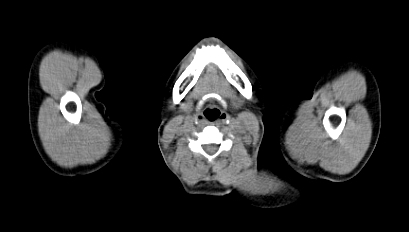

Hình 2 ghi lại kết quả chụp PET/CT của bệnh nhân Trịnh Th. T. L., nữ, 66 tuổi, gần đây thấy xuất hiện ù tai trái, hạch cổ trái. Sinh thiết hạch cổ trái là ung thư biểu mô di căn hạch chưa rõ nguyên phát. Bệnh nhân được chỉ định chụp PET/CT để tìm ổ ung thư nguyên phát.

Hình 2: Hình PET toàn thân và hình PET/CT thấy tổn thương ở vùng vòm (mũi tên đỏ) và hạch góc hàm (mũi tên xanh) tăng hấp thu FDG. Hình ảnh hướng đến ung thư vòm di căn hạch góc hàm trái. Bệnh nhân đi nội soi và bấm sinh thiết vùng vòm trái cho kết quả ung thư biểu mô tế bào vẩy.